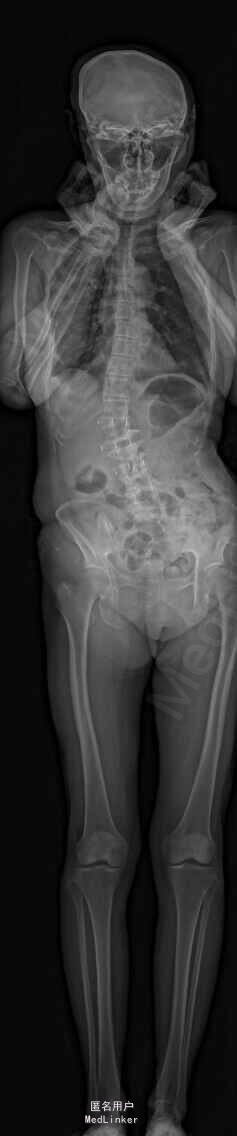

主诉:右下肢麻木伴驼背11年余 病史:患者女性,64岁,11年前无明显诱因出现右下肢疼痛,休息后好转。未予重视,后出现右下肢麻木感,逐渐小狐仙右臀部坚硬,驼背,伴跛行。常感双腿酸胀,腰部疼痛。自行步行距离小于200米,即会发生右下肢僵硬,麻木疼痛。X线检查示腰椎侧弯

查体:脊柱侧弯,上肢无麻木,疼痛感觉异常,腰部右侧疼痛,右下肢及右臀部疼痛,麻木感。双侧肌力及肌张力可,膝腱反射(+),踝反射(+),病理征(—),直腿抬高试验。右侧40度,左侧55度。 辅助检查:腰椎x线片:腰椎侧弯,腰椎退行性改变,L5椎体略行前滑脱 脊柱全长:胸腰段呈S形,L5椎体向前滑脱,L3椎体略变扁,颈胸腰椎退行性改变 MRI:脊柱侧弯,L2-3,L3-L4,L4-L5,L5-S1椎间盘突出,相应节段椎管狭窄

诊断:腰椎侧弯,腰椎椎管狭窄 治疗:手术矫形:早期侧路减压融合,后期再行后路固定。